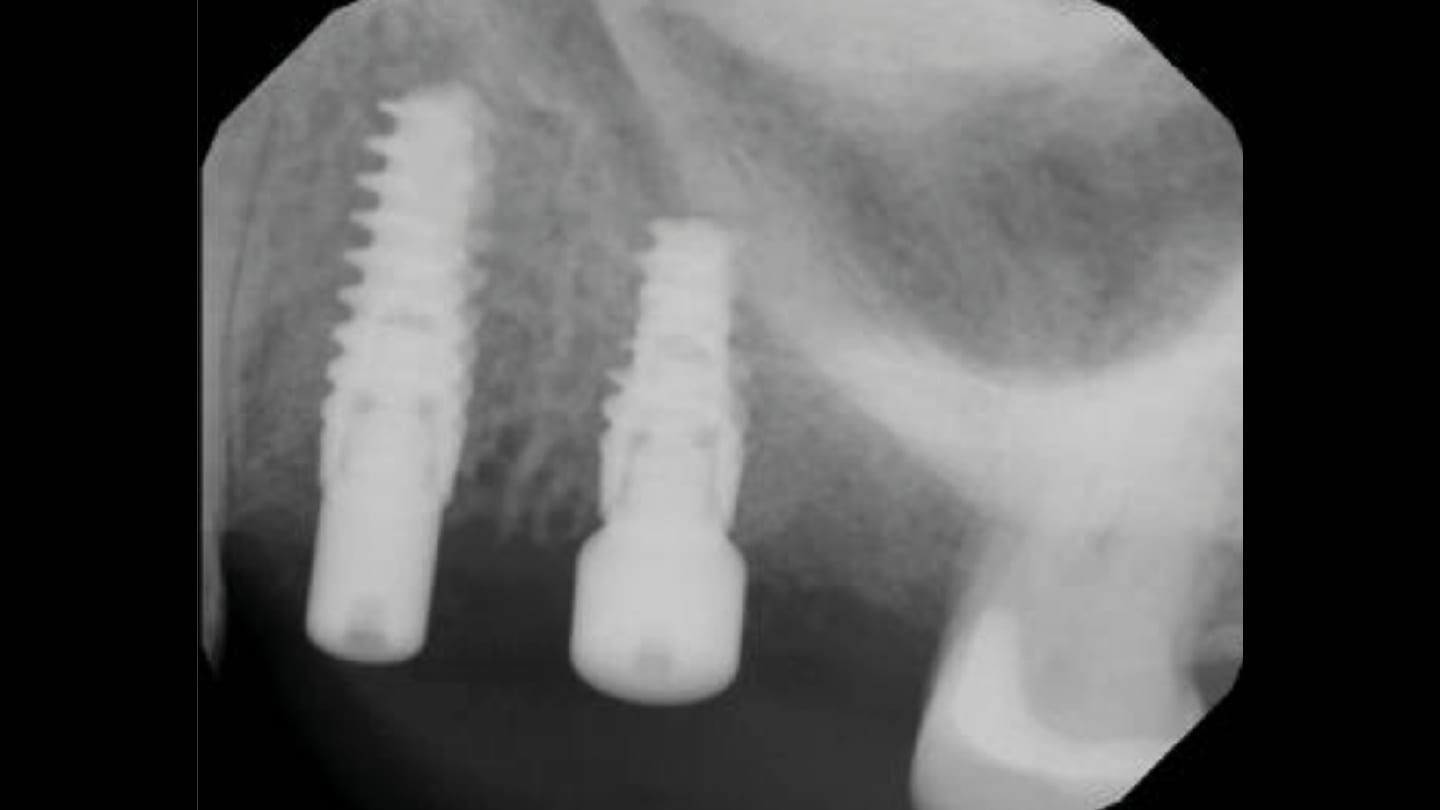

LMHFV, as indicated, may be utilized starting immediately following implant placement when insertion torque dictates or clinical circumstances will not allow immediate loading (Figure 10). Use of LMHFV with the PTech device requires 5 minutes of daily application and accelerates improvements in bone density and osseous healing by stimulating osteogenic cells, growth factors, and angiogenesis, permitting earlier loading. Continued use of LMFHV once loading is initiated will further continue to increase bone density around the implants improving their long-term prognosis through better load handling.59 This also aids in maintaining bone adjacent to the implant when used long-term as part of a daily protocol (Figure 11).

Peri-implantitis is a pathological condition occurring in tissues around dental implants, characterized by inflammation in the peri-implant connective tissue with progressive loss of supporting bone. There is strong evidence that there is an increased risk of developing peri-implantitis in patients who have a history of chronic periodontitis, poor plaque control skills, no regular maintenance care after implant restoration, some chronic medical issues such as diabetes, and other risk factors.60 Peri-implantitis is a common problem, with prevalence rates up to 56%, and without intervention in a timely manner may lead to the loss of the implant.61 The initial presentation may be marginal inflammation or identified radiographically during a routine recall appointment. This may present as horizontal or angular crestal bone loss and a decrease in bone density at the bone-implant interface. Unlike teeth, the presence of mobility with an implant indicates a failed implant and explantation is indicated. In the absence of mobility and when bone loss is minimal, LMHFV may improve the density of the surrounding bone and salvage the implant without the need to intervene with surgery and subsequent grafting. For those clinical situations wherein osseous grafting will be required to cover exposed threads on the implant’s length, LMHFV may be beneficial to improve graft conversion to host bone as with socket grafting by stimulation of osteoblastic activity, growth factors, and angiogenesis.

In the absence of implant mobility, LMHFV can increase the peripheral bone density around the implant at the bone-implant interface that signifies early peri-implantitis. Utilization daily for 5 minutes stimulates growth factors to potentially fill minor defects at the interface while increasing bone density. Following 4 months of use, the clinical situation has improved to aid in elimination of early peri-implantitis when first identified radiographically and surgical intervention has not reached clinical necessity. LMHFV may also be used to supplement surgical intervention when peri-implantitis requires grafting as part of the treatment.